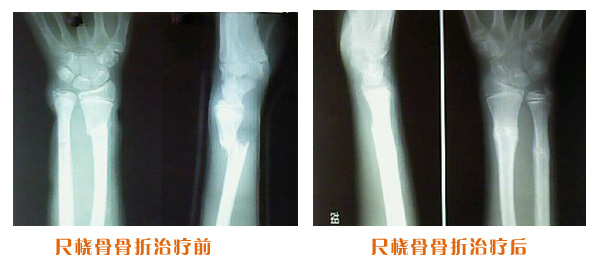

肥城市安駕莊梁氏骨科醫(yī)院是一所以梁氏手法正骨配合膏藥為特色的現(xiàn)代化專科醫(yī)院。